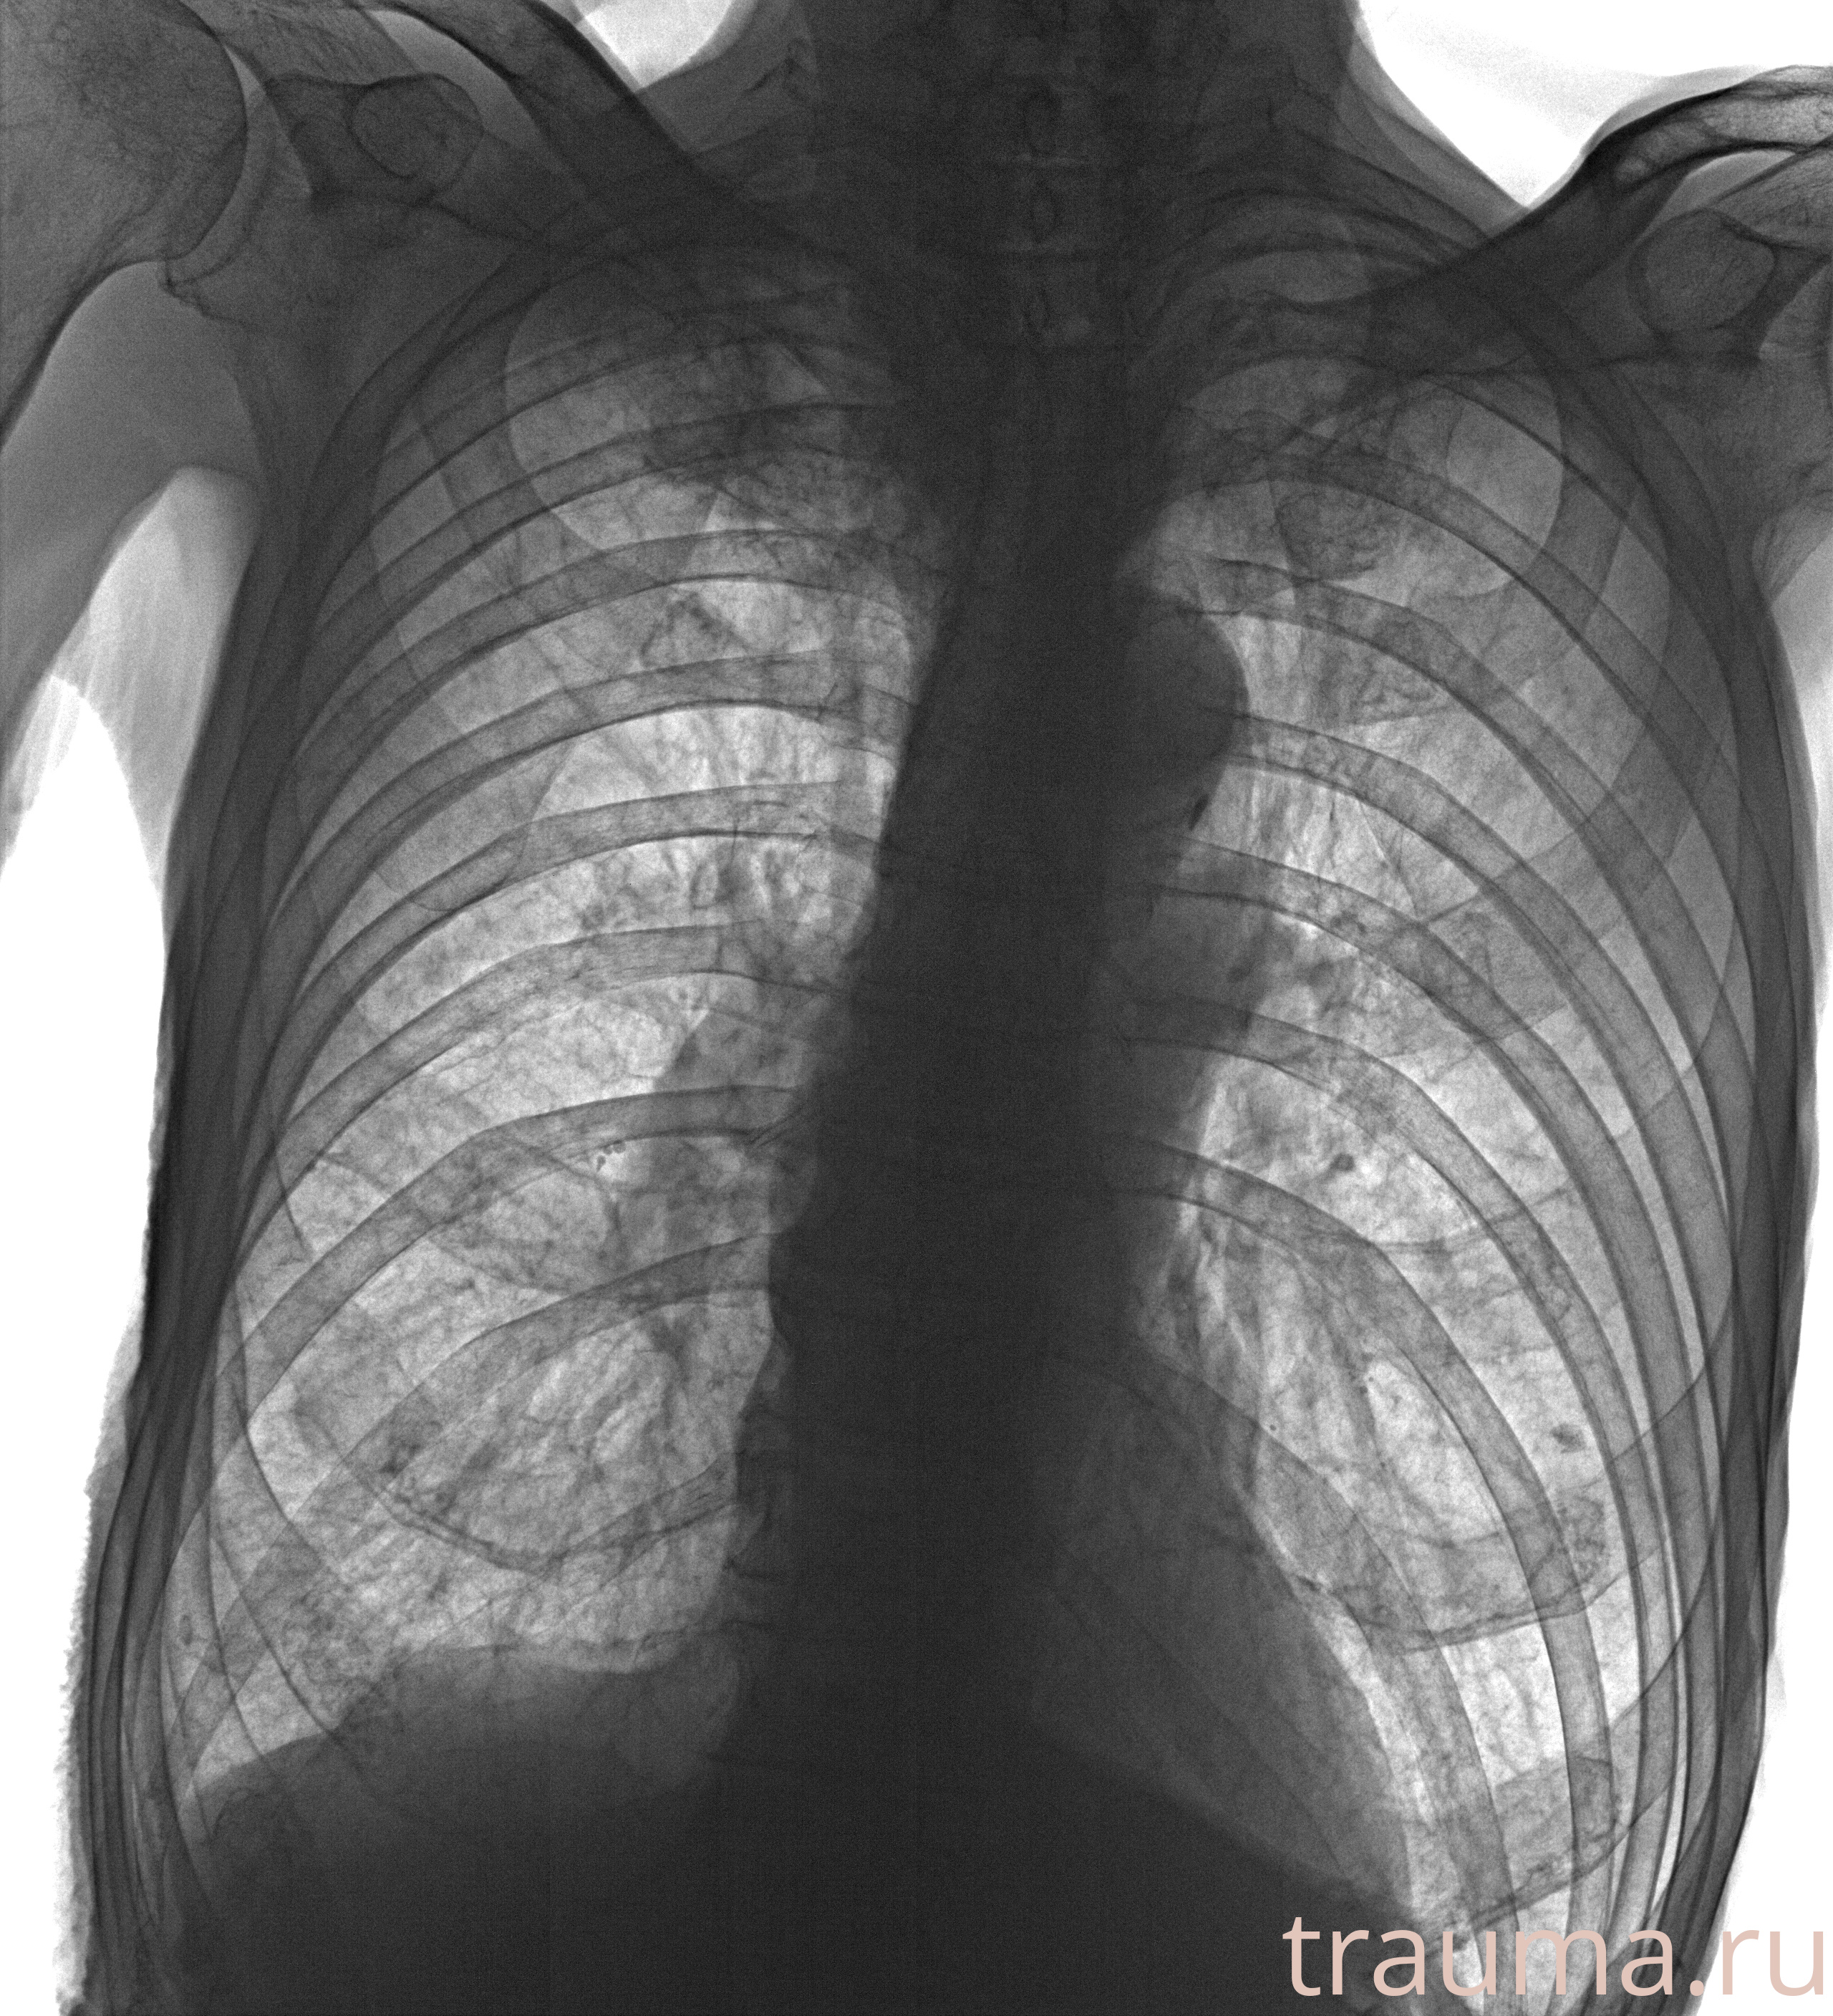

Рентгенограммы

Рентген на дому: по вашему адресу приезжает врач-рентгенолог, травматолог-ортопед с мобильным рентгеновским аппаратом, проводит диагностику травмы или заболевания, делает необходимые рентгенограммы, дает рекомендации по дальнейшему лечению. Получить качественные снимки в домашних условиях возможно благодаря уникальной методике, разработанной МосРентген Центром для института  Склифосовского